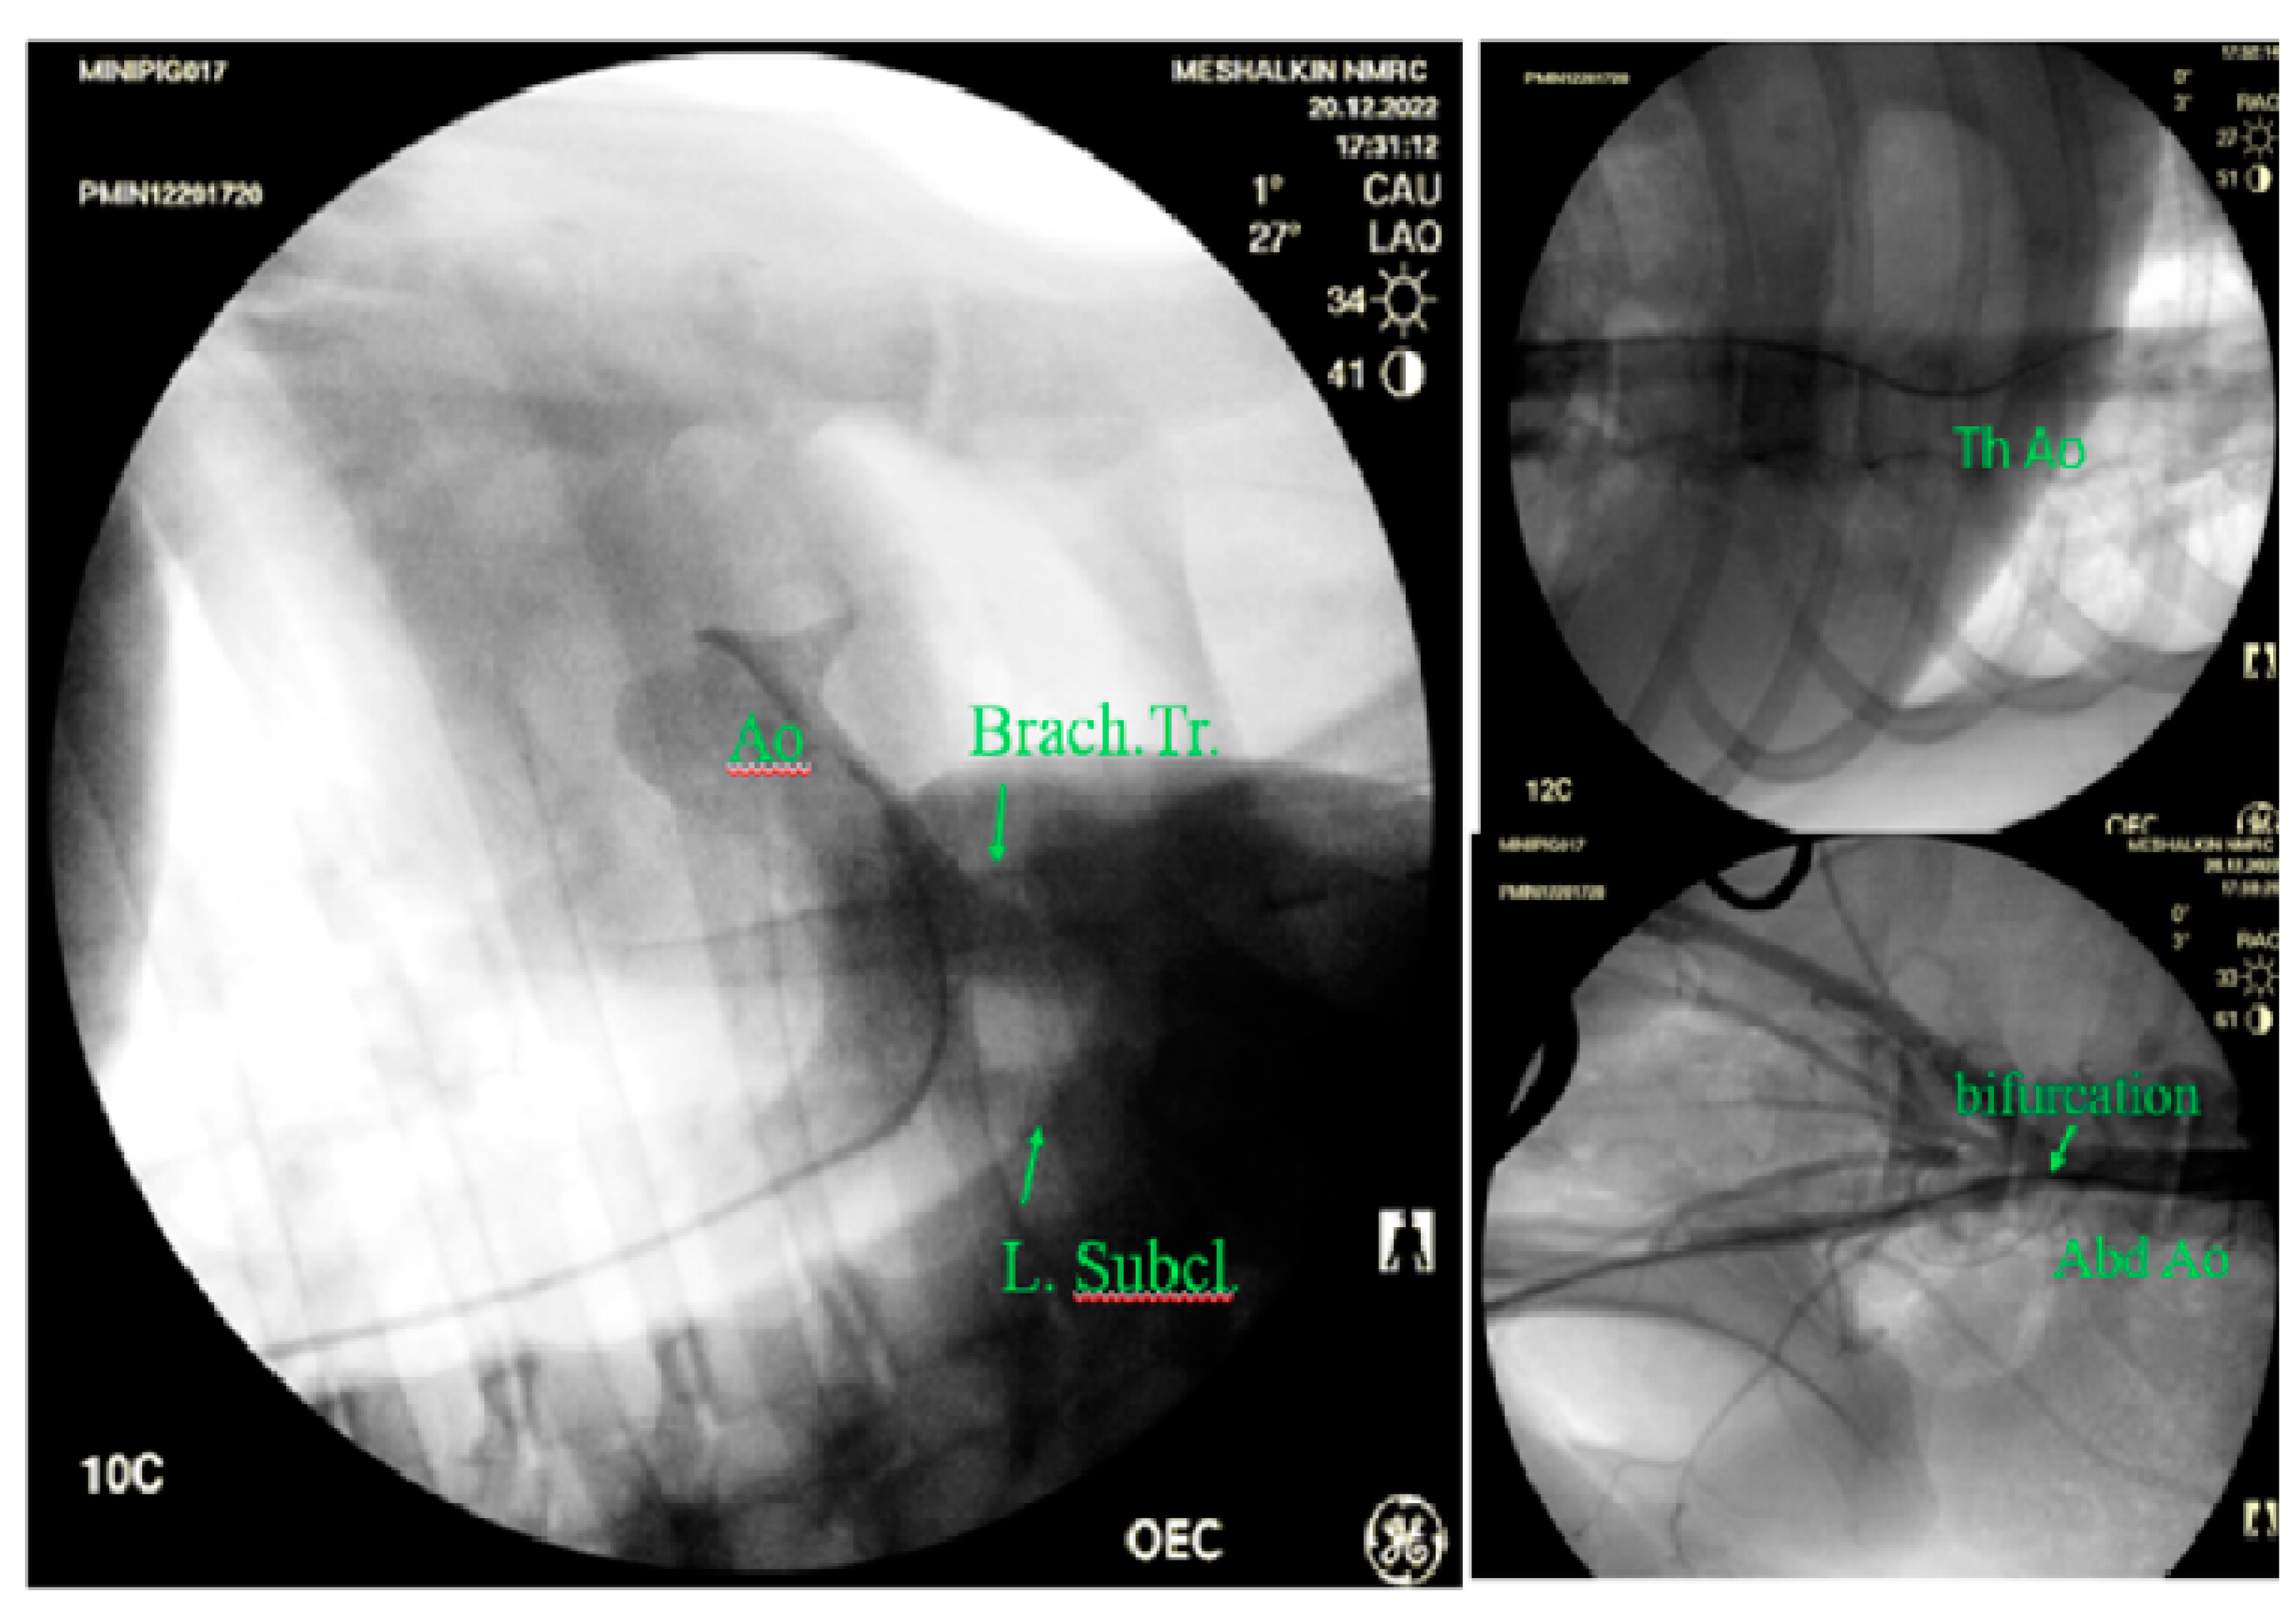

Visualization of the ascending aortic arch, the proximal part of the arch, the subclavian artery and the brachiocephalic trunk was difficult or impossible. Meanwhile angiography made it possible to visualize both the aortic root and its thoracic and abdominal sections at any level before bifurcation (Figure 5).

Figure 5. Visualization of the aorta in its various sections by angiography: Ao -aorta, Brach. Tr.- brachiocephalic trunk, L. Subcl.-left subclavian artery, bifurcation- bifurcation, Abd.Ao - abdominal aorta, Tr Ao- thoracic aorta.